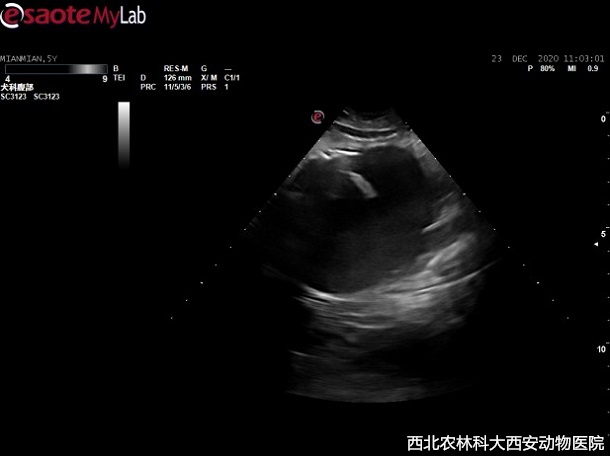

輔助檢查:主人自帶腹部平片顯示前列腺增大,膀胱前列腺區(qū)域有一明顯占位待查。超聲提示:前列腺增生且伴有囊腫,緊鄰前列腺和膀胱可見無回聲異常囊性占位,與周圍組織有聯(lián)系,疑似粘連見(圖1)。

圖一